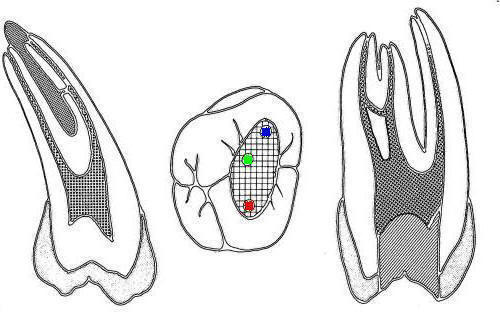

• En azul conducto mesio-vetibular

• En verde conducto mesio-lingual

• En rojo conducto distal

• En amarillo un cuarto conducto,  si el conducto distal se encuentra desplazado hacia lingual, existe una alta posibilidad de encontrar un cuarto conducto

Tres conductos en piso de cámara pulpar, el conducto distal se encuentra ensanchado en sentido buco-lingual, debe sospechar la existencia de dos conductos que comparten el orificio de entrada. Cámara intraoral X10 aumentos.

2º molar inferior (1,2,23,27)

Similar al primer molar inferior pero menos voluminoso, en la raíz mesial siempre encontrará dos conductos y en la raíz distal puede encontrar uno ó dos conductos.

• En azul conducto mesiovetibular

• En verde conducto mesiolingual